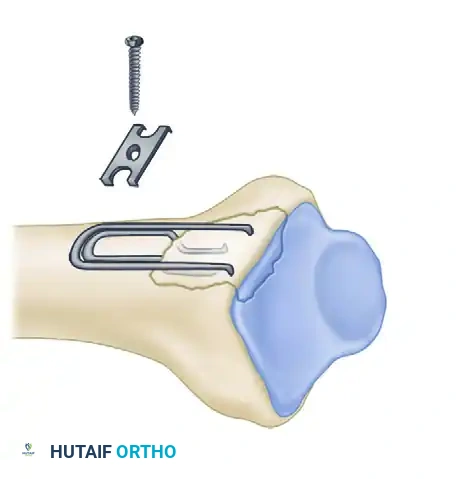

Biomechanics of Pin-Plate Fixation

Traditional radial styloid Kirschner wire fixation provides only a single point of constraint. This single point of fixation acts as a pivot, failing to prevent settling, bending, or radial drift of the distal fragments under physiological loads.

By adding a small buttress plate to the radial styloid pin, the construct is transformed. The pin-plate provides two distinct fixation points: the first through the distal end of the plate, and the second through the intact medial radial cortex. This dual-point constraint prevents collapse, resists dorsal torque, and halts radial migration.

Fragment-Specific Implants and Application

1. The Radial Pin-Plate:

Applied to the radial column, this implant enhances stability by providing a radial buttress. It effectively neutralizes bending forces that would otherwise cause the radial styloid to displace proximally and radially.